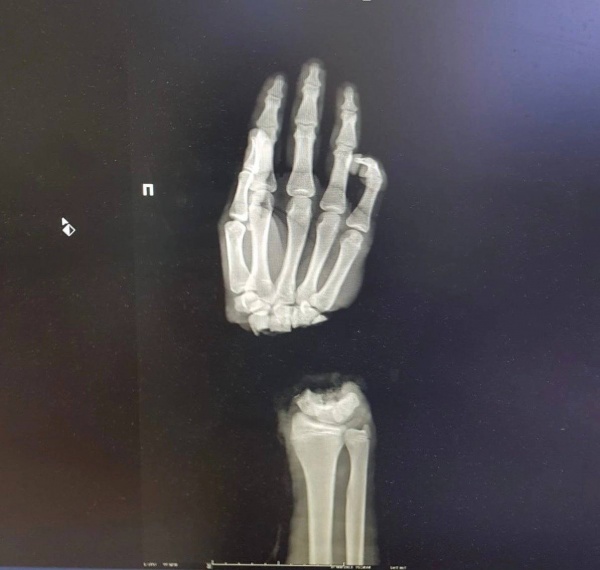

Нижегородские врачи помогли подростку, который отрубил себе кисть руки при колке дров.

Медики провели 16-летнему пациенту операцию по реимплантации конечности. Сейчас его состояние стабильно, кровоснабжение кисти восстановлено. Парню понадобится еще несколько операций, чтобы восстановить функциональность кисти.